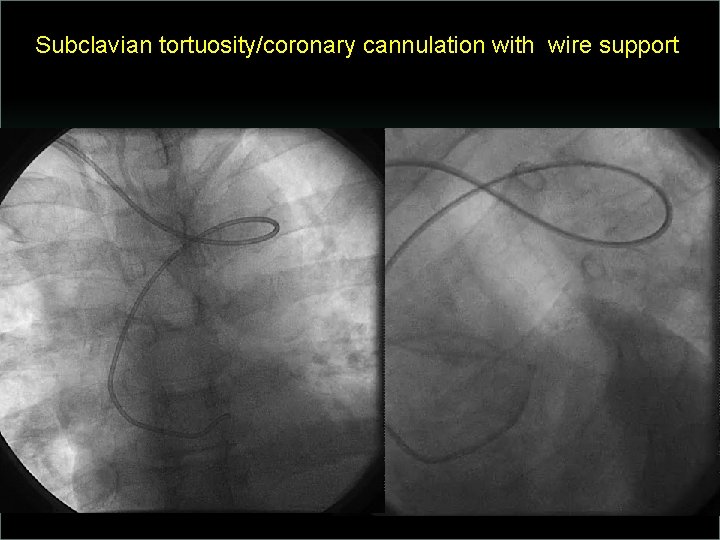

Transradial Interventions Difficult Anatomic Substrate Challenges and Solutions